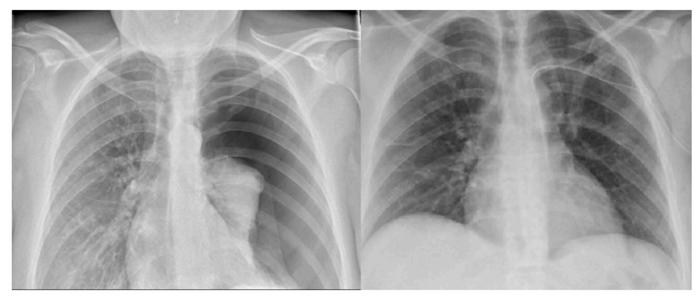

当对诊断有很大把握的时候,查体等也就有了重点。患者查体情况:血压 126/80mmHg。右肺呼吸音弱,左肺呼吸音未闻及。常规心脏听诊部位,心音明显减弱。接下来让患者去拍了胸部正位片(图2)。

妥妥的自发性气胸呀!胸片报告:左侧气胸,肺组织压迫90%,纵膈内积气可能,请结合临床。

我们可以从胸部正位片中看到,该患者在吸憋气的情况下,纵膈(包括心脏)仍然明显向右移位。以上这些因素可能就是导致超声未能经心尖部探及心脏的原因。